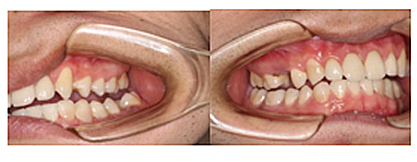

現(xiàn)在剩下的任務就是為我其他的兄弟姐妹們治療了。需要做根管的做根管,需要做冠的做冠,需要樹脂充填的做樹脂充填。前前后后主人帶我們進行了12次的復診,歷時6個月,現(xiàn)在的我們是這樣的

再來看看曾經的我們

經歷了如此長久的治療,主人應該也是吸取了教訓,或許以后會改了不良的生活習慣,而我們經歷了這段涅槃之旅,雖然也煥然一新,重塑了容顏,卻也是歷經辛苦,如果主人能好好待我們,其實這樣的痛苦本不需要經歷。